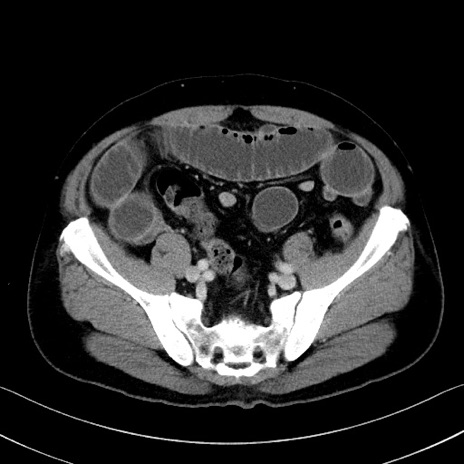

症例35(横断像)

【症例】70歳代 男性

【主訴】腹部膨満、嘔吐

【現病歴】昨日より腹部膨満感出現。本日増悪し、仙痛出現。嘔吐あり、受診。

【既往歴】糖尿病、胆摘後

【身体所見】BP 149/80mmHg、HR 74/min、BT 35.9℃、腹部:膨満、軟、圧痛なし。腸雑音減弱あり。上腹部正中切開瘢痕あり。

【データ】WBC 13500、CRP 1.72